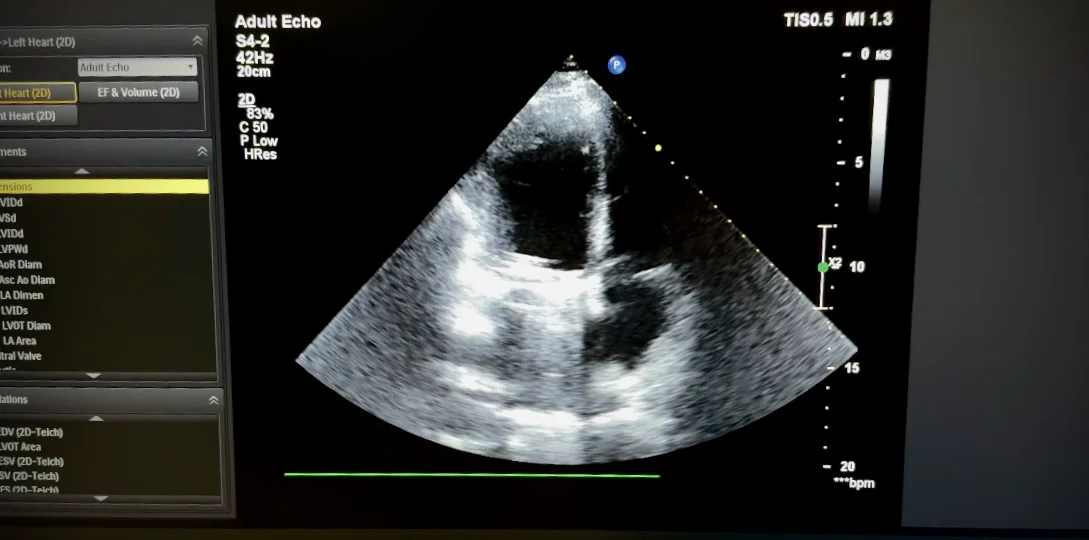

Внаслідок тривалого перебігу захворювання сформувалося ускладнення: відносна недостатність тристулкового клапана (див. фото 3).

Таким чином, маємо двоклапанну патологію: тяжка мітральна недостатність та вторинна тристулкова недостатність.